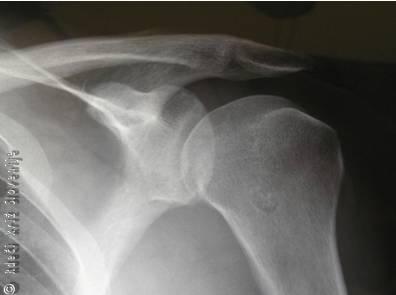

Slika 2

Rentgenska slika ramenskega obroča.